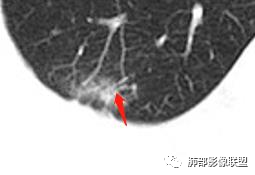

1、对于这个胸膜凹陷处局限性突起,类似于毛刺征,这是我们的误区,也是个假象。

2、横断位你发现很多粗短毛刺:但是矢状位冠状位没发现了,是假的,所以我们要多方位、连续层面观察。3、支气管:进入病灶内的局部支气管扩张,符合炎症的。

5、空洞:内壁光滑,近肺门侧空洞就是肺结核,肿瘤坏死是远端的,炎症都可以朝结核方面类似的;壁结节:如果层面稍微皱褶点,某些层面就成了壁结节。